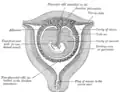

Plano seccional de um útero gravídico no terceiro e quarto mês

Plano seccional de um útero gravídico no terceiro e quarto mês -